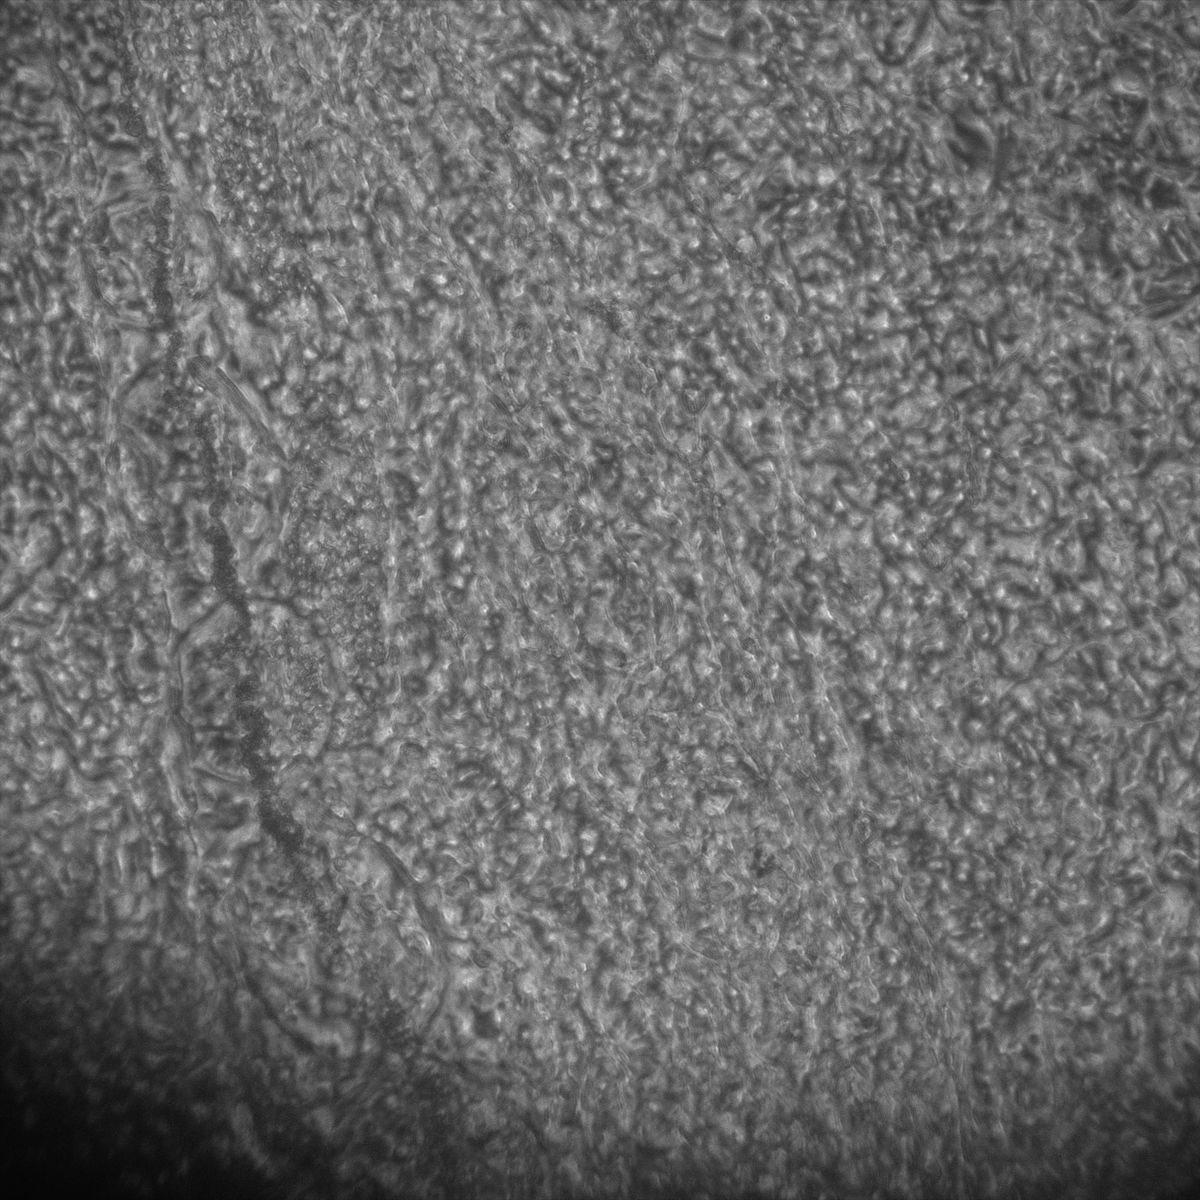

Healthy Choroid

Unhealthy Choroid